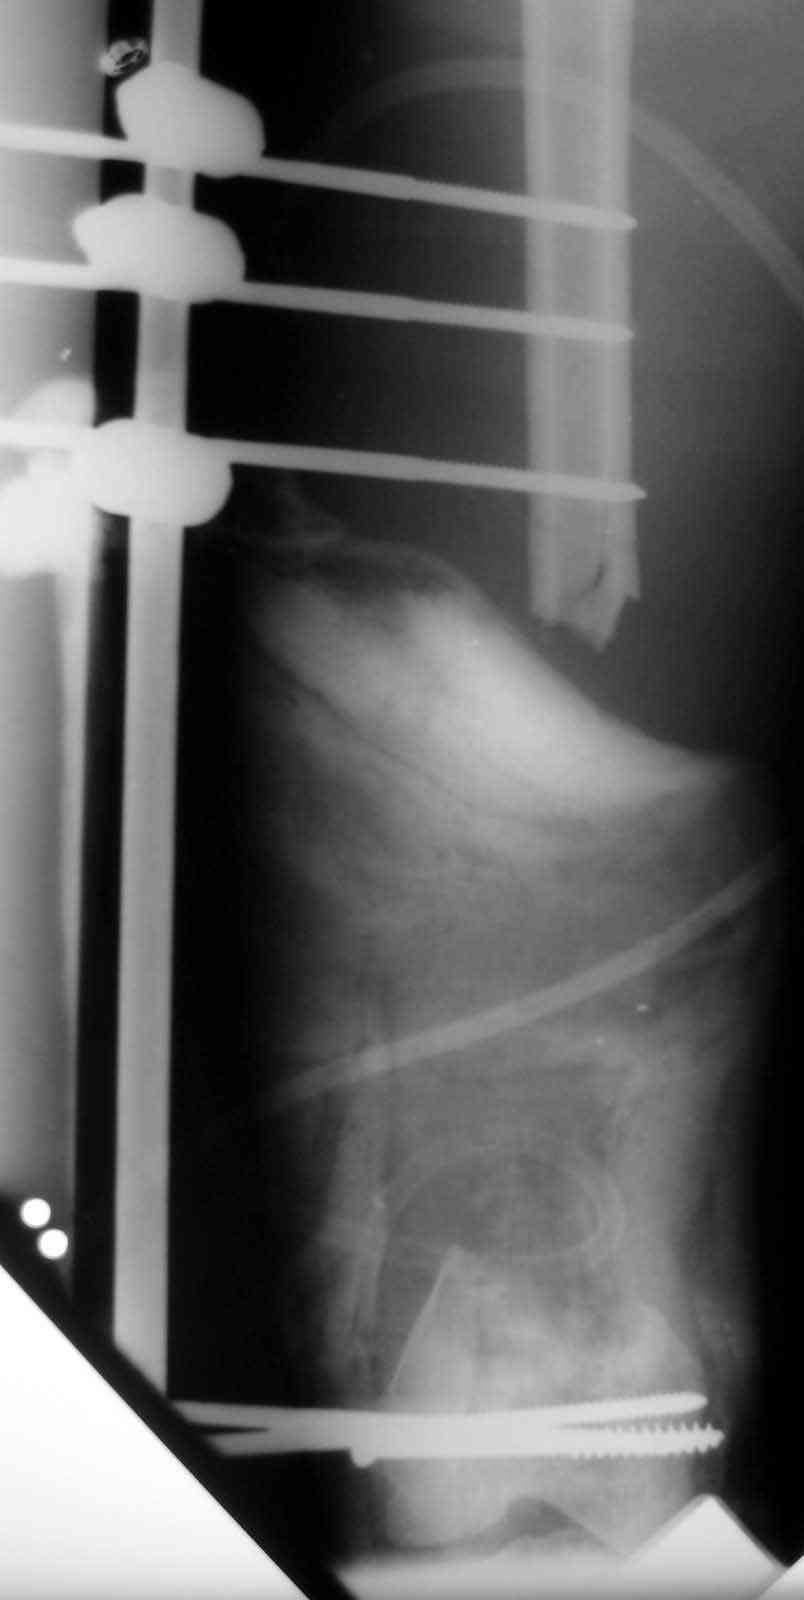

Lost 1/2 of femur

18 ys. old boy with motorcycle accident lost the distal 1/2 of his femur at the scene of the accident.

Debridment and ex. fix done immediately. full details and x-rays are here :